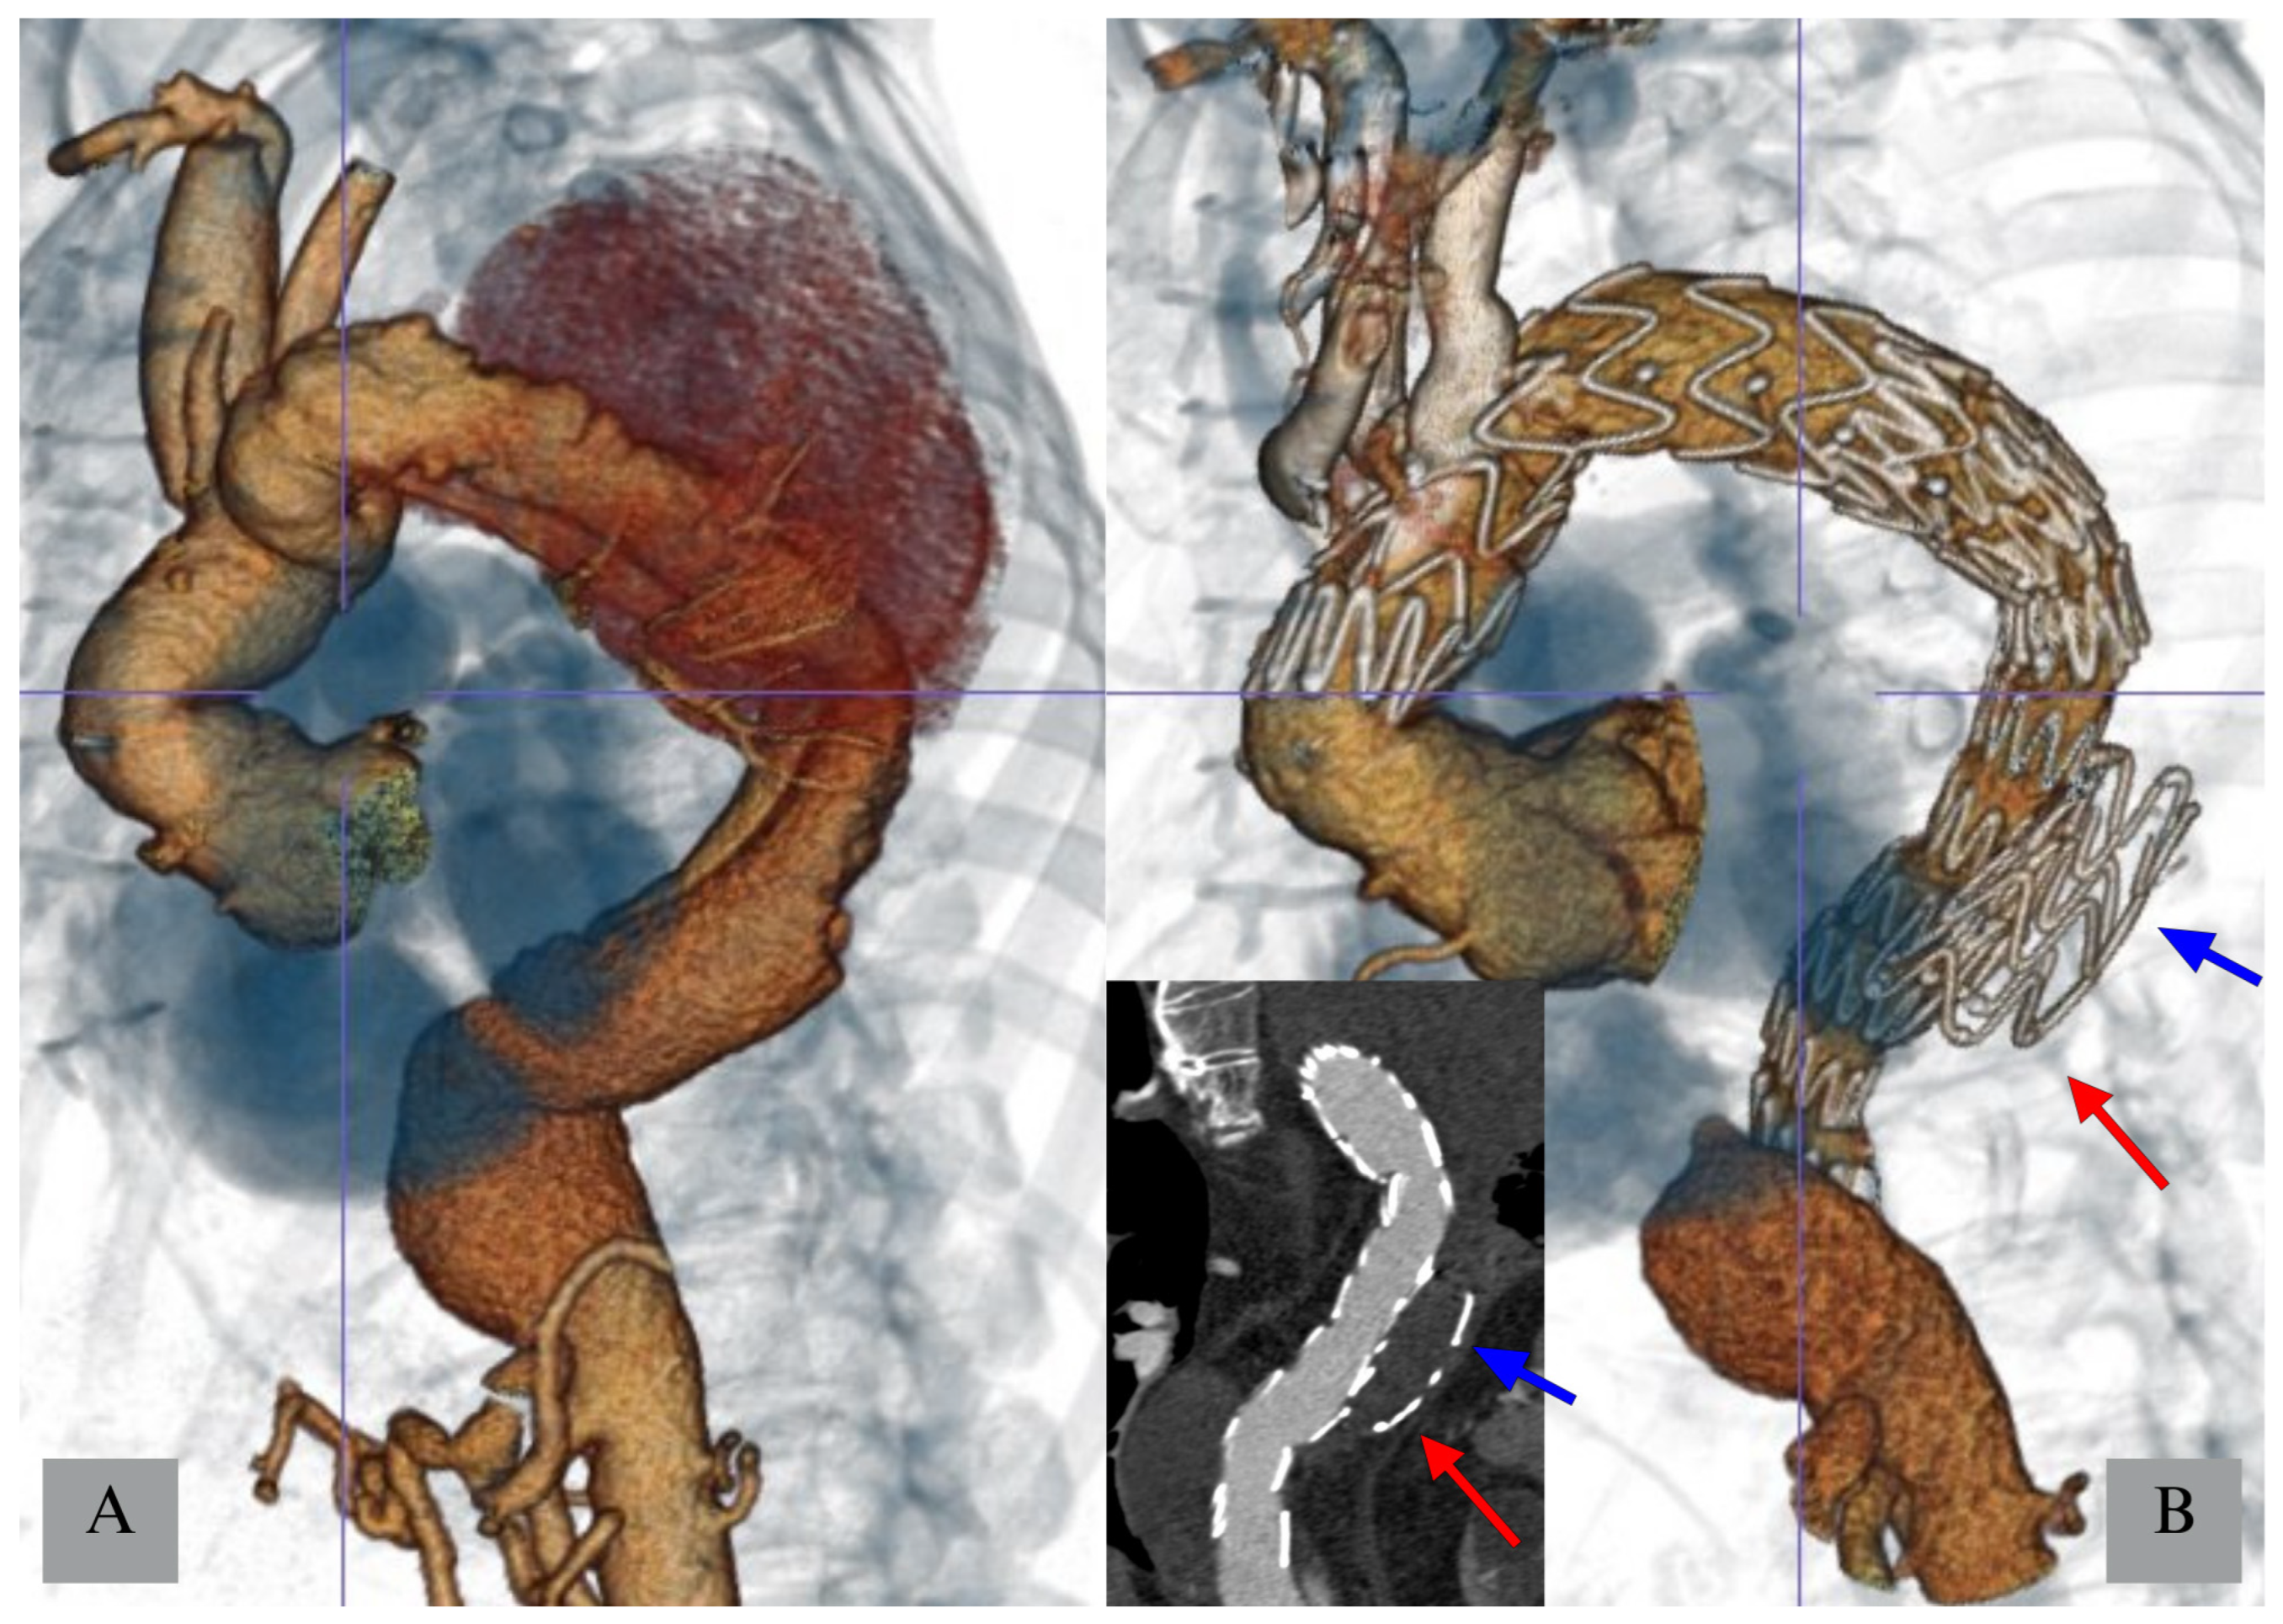

3.1.2. Temporary Aneurysm Sac Perfusion (TASP)

- Kasprzak, P.M.; Gallis, K.; Cucuruz, B.; Pfister, K.; Janotta, M.; Kopp, R. Editor’s choice—Temporary aneurysm sac perfusion as an adjunct for prevention of spinal cord ischemia after branched endovascular repair of thoracoabdominal aneurysms. Eur. J. Vasc. Endovasc. Surg. 2014, 48, 258–265. [Google Scholar] [CrossRef]

- Youssef, M.; Salem, O.; Dünschede, F.; Vahl, C.F.; Dorweiler, B. Adjunct Perfusion Branch for Reduction of Spinal Cord Ischemia in the Endovascular Repair of Thoracoabdominal Aortic Aneurysms. Thorac. Cardiovasc. Surg. 2018, 66, 233–239. [Google Scholar] [CrossRef]

- Jayia, P.; Constantinou, J.; Hamilton, H.; Ivancev, K. Temporary Perfusion Branches to Decrease Spinal Cord Ischemia in the Endovascular Treatment of Thoraco-Abdominal Aortic Aneurysms. AORTA 2015, 03, 56–60. [Google Scholar] [CrossRef]

- Harrison, S.C.; Agu, O.; Harris, P.L.; Ivancev, K. Elective sac perfusion to reduce the risk of neurologic events following endovascular repair of thoracoabdominal aneurysms. J. Vasc. Surg. 2012, 55, 1202–1205. [Google Scholar] [CrossRef] [PubMed]

- Mangialardi, N.; Lachat, M.; Esposito, A.; Puippe, G.; Orrico, M.; Alberti, V.; Fazzini, S.; Ronchey, S. The “Open Branch” Technique. Catheter. Cardiovasc. Interv. 2016, 87, 773–780. [Google Scholar] [CrossRef] [PubMed]

- Lioupis, C.; Corriveau, M.M.; MacKenzie, K.S.; Obrand, D.I.; Steinmetz, O.K.; Ivancev, K.; Abraham, C.Z. Paraplegia prevention branches: A new adjunct for preventing or treating spinal cord injury after endovascular repair of thoracoabdominal aneurysms. J. Vasc. Surg. 2011, 54, 252–257. [Google Scholar] [CrossRef]